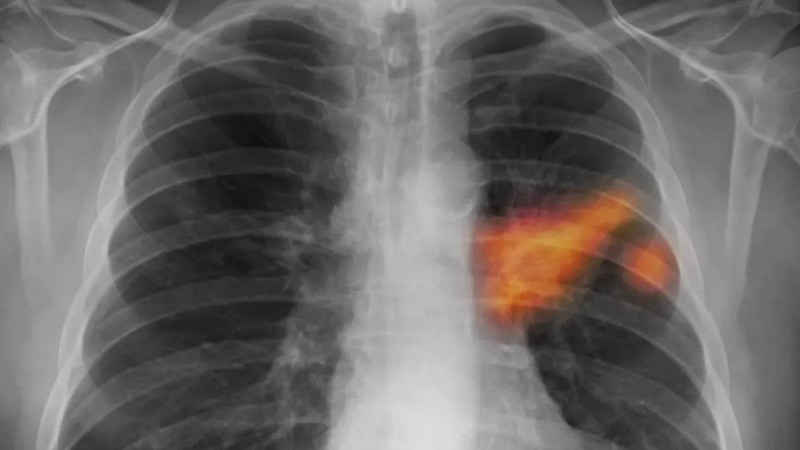

Tomáš Řehoř (57) z Prahy, bývalý kuřák, podstoupil preventivní vyšetření na doporučení lékařky, které odhalilo nezhoubný nádor na plicích, ačkoliv neměl žádné potíže, což dokazuje důležitost včasného screeningu rakoviny plic. #screeningrakoviny #zdraví #prevencetruchu #dobrezpravy

Rok co rok je rakovina plic odhalena u více než 6500 pacientů, přičemž pouze u jednoho z deseti je diagnóza stanovena včasné léčitelném stádiu, přičemž preventivní screening pomůže každému druhému vyšetřenému, avšak polovina oslovených na něj nedochází a praktický lékaři tento vyšetřovací program nabízejí jen polovině svých pacientů. #rakovinaplic #screening #prevencetumoru